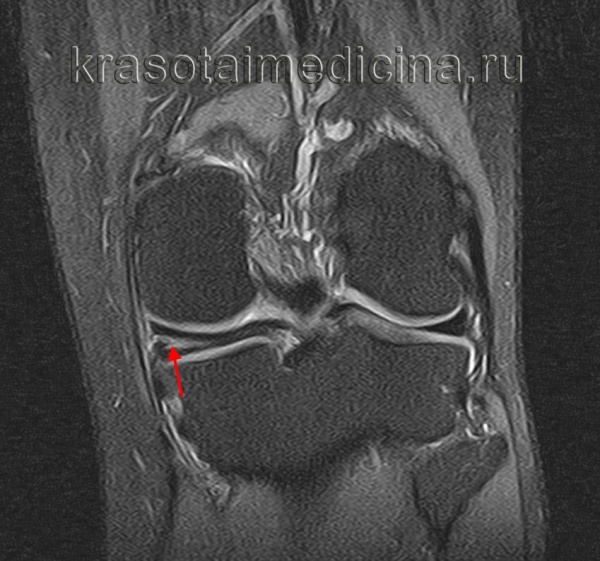

Для более точного определения тяжести повреждений применяется классификация по Stoller, основанная на объективных критериях, выявляемых при помощи магнитно-резонансной томографии. Согласно данной классификации выделяется 4 степени повреждения – от 0 (изменений нет) до 3 степени (полный разрыв).

МРТ применяется для определения малейших изменений в хрящевой ткани, а также классификации степени тяжести по Stoller. Артроскопия представляет собой инвазивный метод исследования с непосредственным осмотром структур колена при помощи артроскопа (оптический прибор в виде тонкой трубки, который оснащен видеокамерой, он вводится в полость сустава).